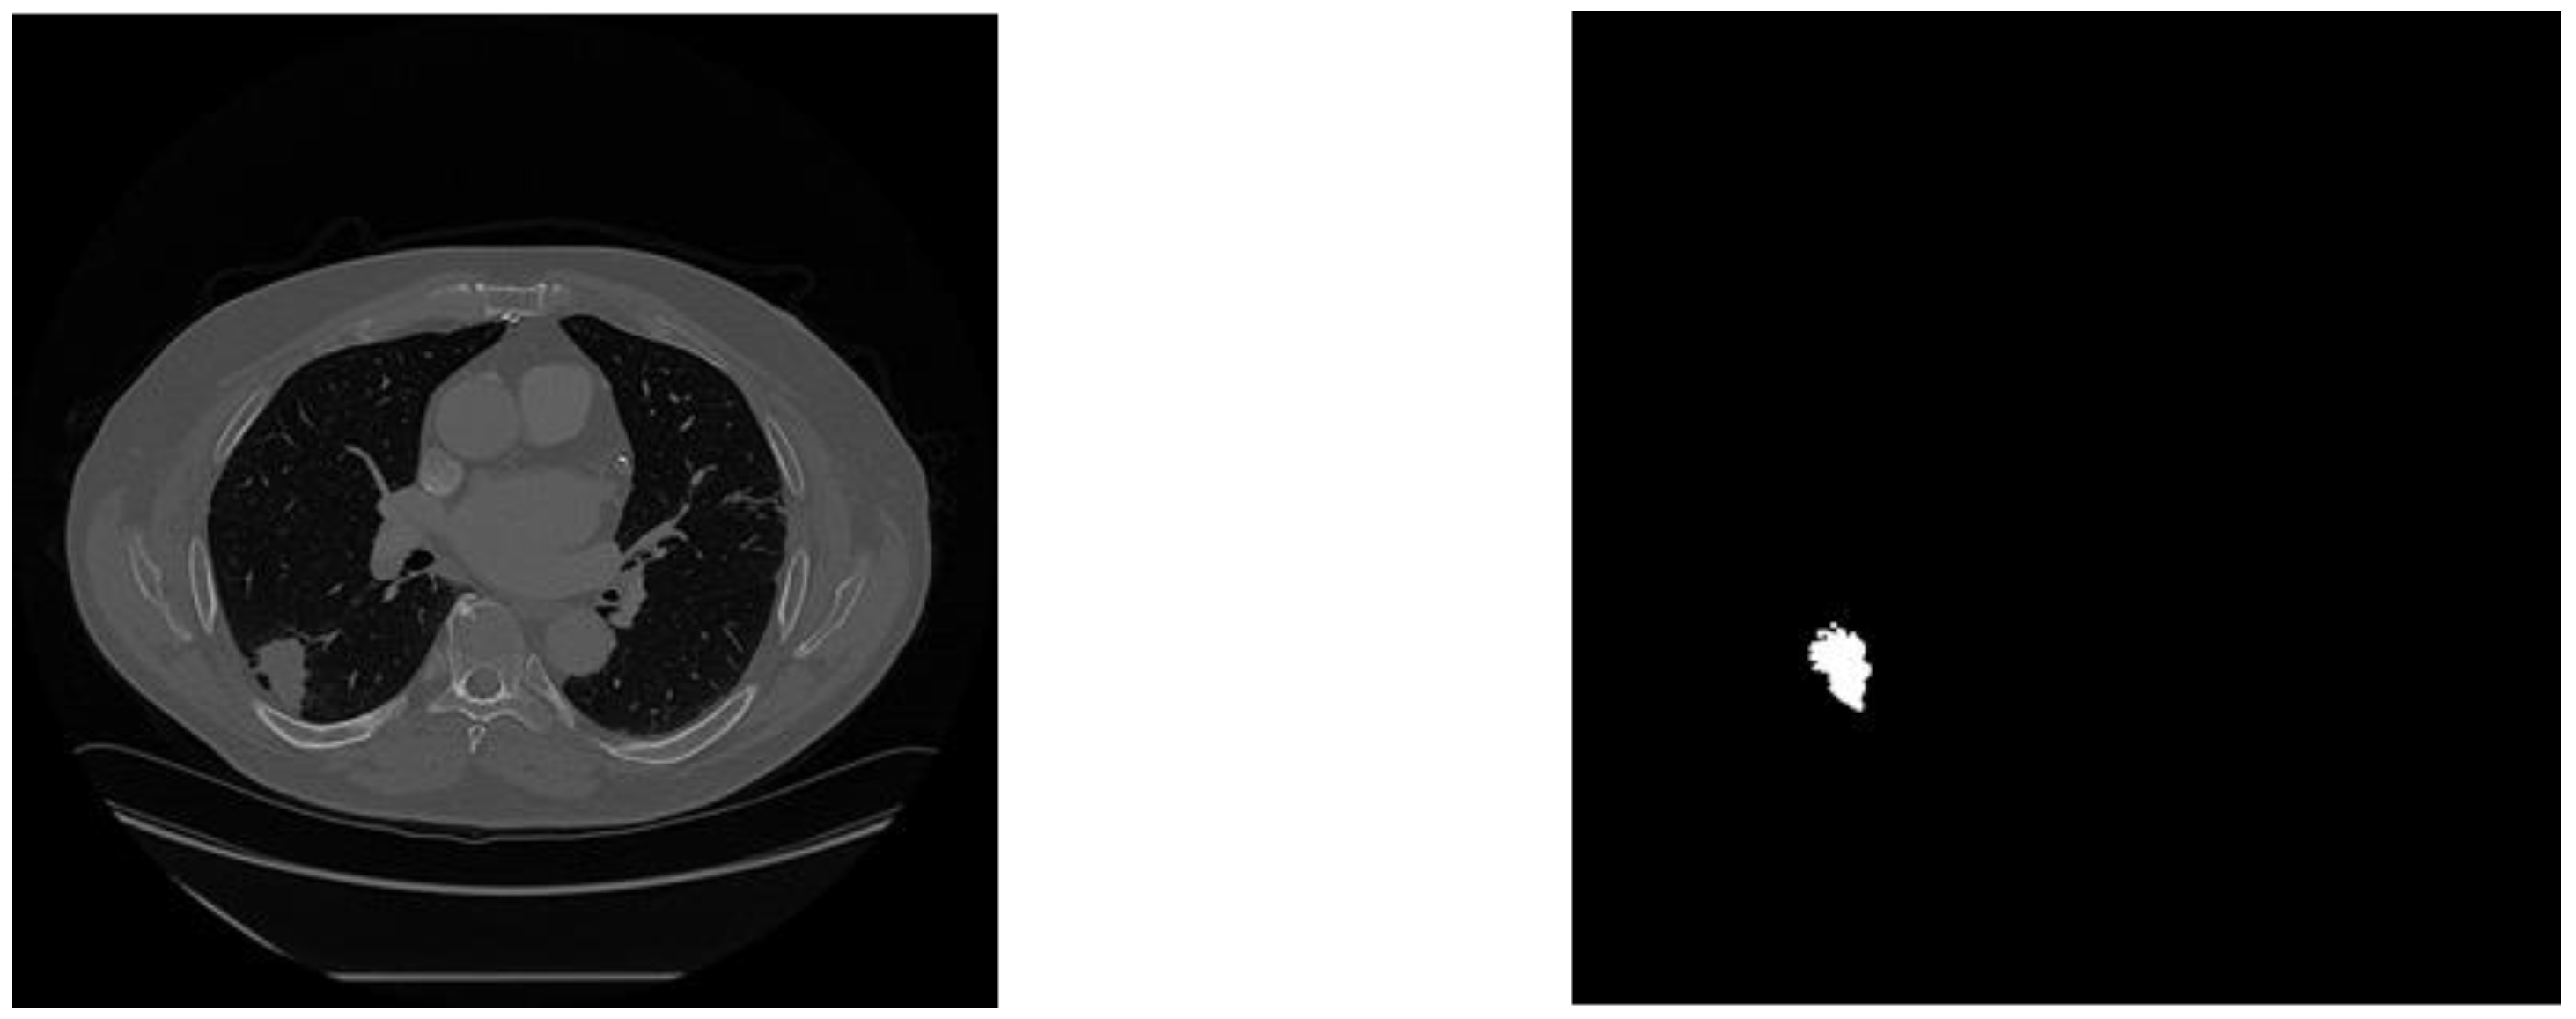

Figure 2. View of original 3D CT scan with its corresponding mask from MSD dataset.

Each Nifti (NII) file was split along the z-axis into 300-700 slices at 512x512 resolution using the med2image library. Conversion of all scans resulted in 17,000 slices, 90% of which did not contain a visible tumor in the corresponing mask. Data was filtered to only keep those with the tumor, resulting in 1756 files. The original dataset (In 3D) was 13 gigabytes, and the new dataset was 356 megabytes (36.5x smaller).

Figure 4. Example training image with its corresponding mask.